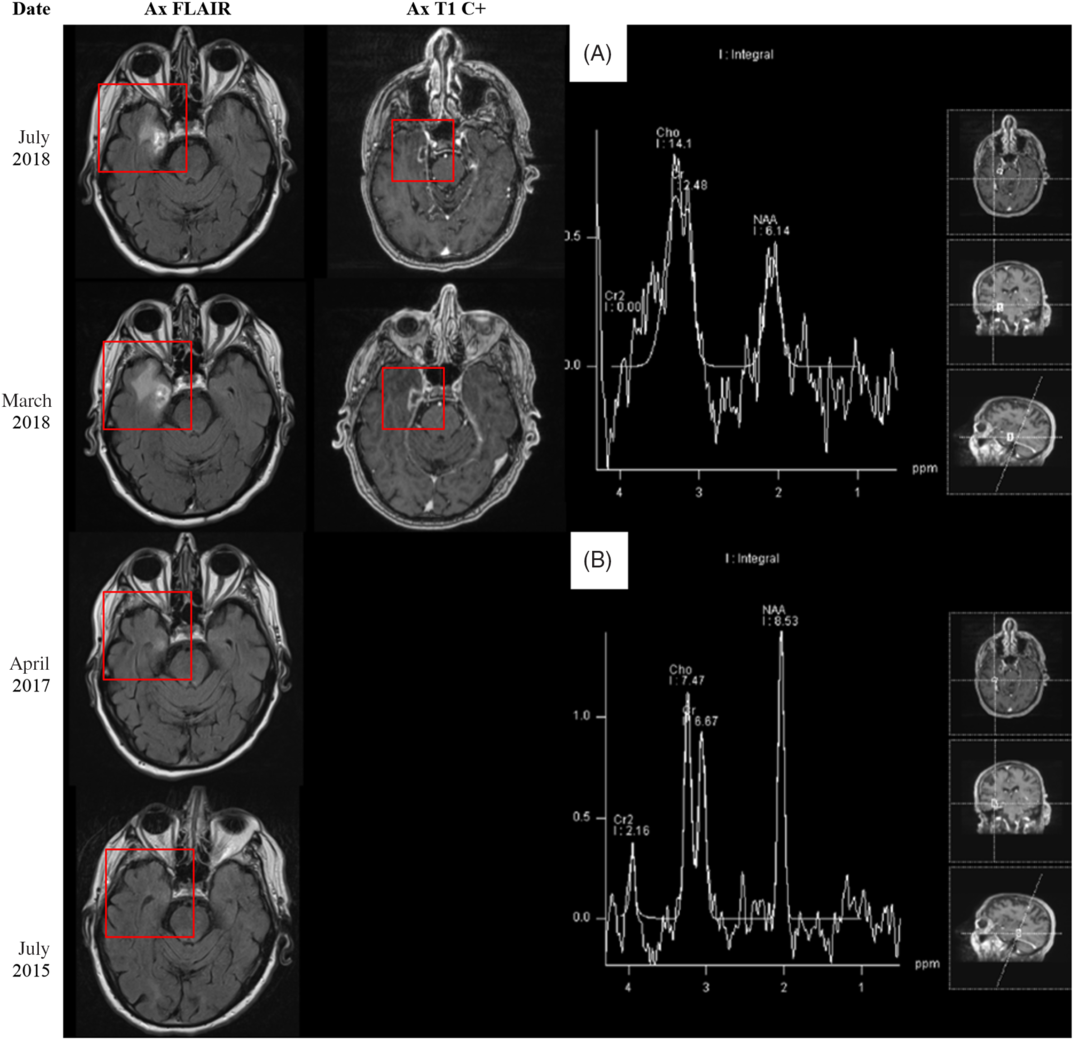

In April 2017, the patient presented with dysarthria and right-sided weakness; a diagnosis of acute ischemic stroke was made. The patient experienced some improvement in the emergency room, and tissue plasminogen activator was not administered. MRI (Figure 2) incidentally revealed a right temporal fluid-attenuated inversion recovery (FLAIR) hyperintensity. A follow-up MRI 10 months later in March 2018 (Figure 2) revealed a new ring-enhancing lesion within this area. Given the interval development, the patient was diagnosed with presumed high-grade glioma. At this time, his symptoms included constant right-sided facial pain, right hemifacial numbness in V 1-3, and a mild facial droop.

Figure 2: (Left side) MRI 5 months before, 16 months after, 27 months after, and 31 months after stereotactic radiosurgery (SRS) to the right Gasserian ganglion in December 2015. (Right side) MRS findings 31 months after SRS treatment to the right Gasserian ganglion in December 2015. (A) Area of abnormal contrast enhancement. (B) Normal brain parenchyma.

Repeat MRI demonstrated marginal interval decrease in the peripheral enhancement and vasogenic edema of the temporal lesion. At this point, the possibility of radiation necrosis rather than high-grade glioma was entertained. The patient refused all interventions, including a stereotactic biopsy for tissue diagnosis. A noninvasive approach – magnetic resonance spectroscopy (MRS) – was pursued for better characterization of the lesion (Figure 2). On MRS, there was decreased N-acetyl-aspartate (NAA) within the involved region of abnormal contrast enhancement. The choline (Cho) levels remained within relatively normal limits with respect to both ipsilateral normal brain parenchyma and creatine (Cr) levels as a reference standard. These findings suggested decreased neuronal activity without significant elevation of cell membrane turnover, resulting in relatively preserved Cho/Cr ratio but increased Cho/NAA ratio in the region of interest. Although, in radiation necrosis, one would expect to see a slight decrease in both NAA and Cho, the lack of significant increase in Cho still favors radiation necrosis over high-grade glioma.

Several studies have compared more advanced imaging techniques.Reference Chuang, Liu, Tsai, Chen and Wang3 Shah et al. found that single-photon emission computed tomography has the highest specificity (97.8%); meanwhile, MRS has good sensitivity (85.9%) and specificity (79.9%).Reference Shah, Snelling and Bregy2 Zhang et al. studied MRS in particular and found that metabolite ratios Cho/NAA (sensitivity 88%; specificity 86%) and Cho/Cr (sensitivity 83%; specificity 83%) were both useful in distinguishing radiation necrosis from glioma recurrence.Reference Zhang, Ma, Wang, Zheng, Wu and Xu4

A literature review identified one previously reported case of radiation necrosis following stereotactic radiosurgery for trigeminal neuralgia.Reference Montoure, Zaidi, Sheehy, Shetter and Spetzler5 In Montoure et al.’s report, the patient had undergone TomoTherapy for trigeminal neuralgia 1 year prior to the development of a ring-enhancing lesion in the mesial temporal lobe (Table 1). The authors performed a supratotal resection of the lesion and a final diagnosis of radiation necrosis was made based on histological examination. When comparing the two cases, a number of differences and similarities are noted. Both patients were treated with stereotactic radiosurgery for refractory trigeminal neuralgia. Montoure et al’s case involved a total of 40 Gy of TomoTherapy radiation in two equally divided doses; our patient underwent a total dose of 110 Gy of CyberKnife radiation divided in two unfractionated doses 2 years apart; the mesial temporal lobe, depending on the location, received up to 5.5 Gy on the first treatment and up to 33 Gy in the second treatment – after analyzing the radiosurgery treatment plans, it appears that the area of suspected radiation necrosis likely received minimal radiation from the first treatment and up to 11 Gy from the second treatment (Figure 1). Both patients developed symptoms within 1–2 years. MRI findings were nearly identical. Montoure et al.’s case was diagnosed with tissue biopsy, while this case was diagnosed by a combination of clinical characteristics and radiographic evidence (MRI and MRS). A comparison is summarized in Table 1.